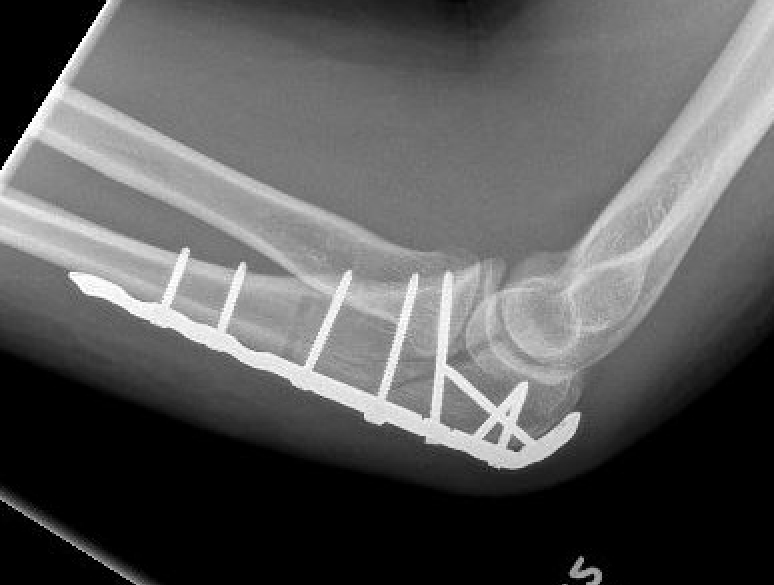

Technique

ORIF olecranon with plate +/- LCL repair

- posterior approach and plate olecranon

- reassess stability

Olecranon plate + ORIF Type II coronoid process + radial head replacement

Olecranon plate with radial head replacement